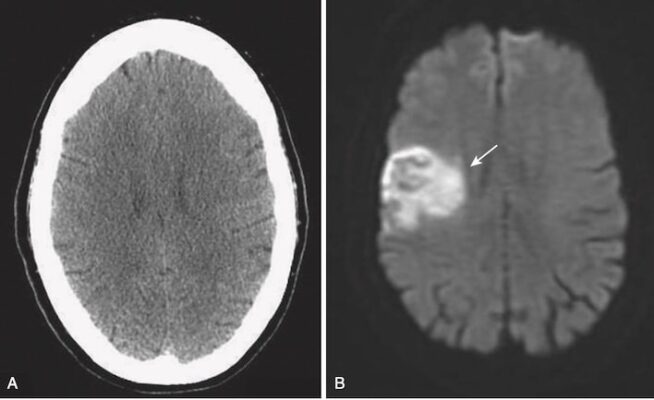

A, Chụp CT ở bệnh nhân này với các triệu chứng trong 2 giờ trước khi nghiên cứu là bình thường.

B, Chụp MRI khuếch tán trên cùng một bệnh nhân vài phút sau cho thấy một vùng có cường độ tín hiệu sáng bất thường ở vùng chẩm trán bên phải (mũi tên trắng). Hình ảnh khuếch tán (Diffusion-weighted imaging, DWI) là một chuỗi xung MRI có thể được thu nhận nhanh chóng và cực kỳ nhạy để phát hiện các bất thường trong chuyển động bình thường của nước trong não do đó có thể xác định đột quỵ trong vòng 20 đến 30 phút sau khi sự kiện xảy ra.